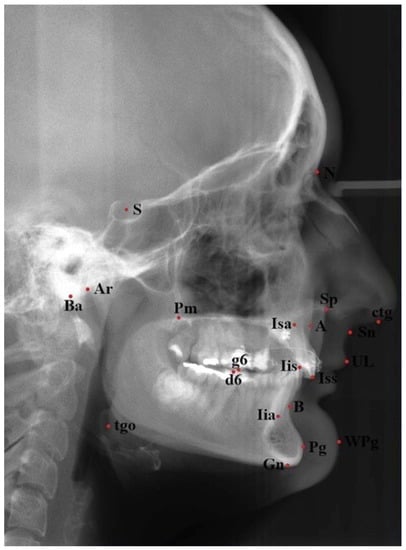

| Abbreviation | Mean Value | Interpretation | Special Significance in Cleft Palate (Only) |

|---|---|---|---|

| SNA | 82 | Sagittal maxillary position referring to cranial base. | Negative—indicates sagittal maxillary deficiency. |

| SNB | 80 | Sagittal position of the mandibular alveolar part referring to cranial base. | Reduced in mandibular deficiency. |

| ANB | 2 | Sagittal relation between the maxilla and mandible. | Negative in sagittal maxillary deficiency referring to mandible, reduces with age due to normal growth. |

| SNPg | 82 | Sagittal position of the chin referring to cranial base. | Reduced in mandibular deficiency. |

| NL-NSL | 8 | Vertical maxillary inclination relative to cranial base. | Reduced in vertical maxillary deficiency. |

| ML-NSL | 28 | Vertical mandibular inclination relative to cranial base. | Increased in posterior rotation of the mandible. |

| ML-NL | 20 | Vertical jaw relation. | Increased in posterior rotation of the mandible and in vertical maxillary deficiency. |

| NS-Ba | 130 | Inclination of the clivus to cranial base. | _ |

| Gn-tgo-Ar | 122 | Gonial angle. | Increased in severe mandibular deficiency with posterior rotation |

| H | 9.2 | Angle between the line upper lip—soft-tissue chin relative to line NB—inclination of the soft tissue profile. | Reduced in upper lip retrusion associated by maxillary deficiency, reduces with normal growth. |

| 1+:1- | 133 | Angle between the long axes of upper and lower central incisors. | _ |

| 1+:NA | 21 | Upper incisor inclination to NA line. | Increased with protrusion of upper incisors (compensatory to sagittal maxillary deficiency). |

| 1+:NB | 24 | Lower incisor inclination to NB line. | Reduced with retrusion of the lower incisors (compensatory to sagittal jaw discrepancy) |

| Nasolabial angle | 110 | Angle between nasal base and upper lip. | Increased in sagittal maxillary deficiency. |

| Index | 80 | Proportion between the upper and lower face height (in percentage). | Reduced in vertical maxillary and midface deficiency, reduced in posterior mandibular rotation. |

| Pg:NB (mm) | 2.3 | Distance between the point Pg and NB line. Describes chin prominence. | Reduced in mandibular Deficiency |

| 1+:NA mm | 4 | Distance between the incisal edge of the upper central incisor and NA line. | Increased in protrusion of upper incisors (compensatory to sagittal maxillary deficiency). |

| 1-:NB mm | 3.8 | Distance between the incisal edge of the lower central incisor and NB line. | Reduced in retrusion of lowers incisor (compensatory to sagittal jaw discrepancy). |

| Wits (mm) | 0 | Distance between perpendicular projections of points A and B on the occlusal plane. | Negative value in maxillary deficiency. |